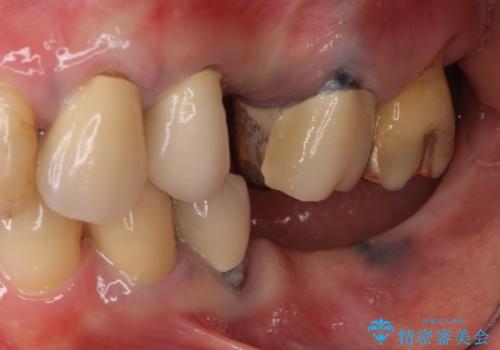

- 奥歯が痛いことを主訴にご来院された患者様です。入院してしまい、治療を2年間放置してしまったとのことでした。

左上は、抜歯とブリッジ治療を行いました(抜歯前に医師と対診)。

左下は、現在も抗がん治療を続けているため、観血的処置(インプラントなどの外科)はなるべく避けたいとのことで入れ歯を希望されました。それに伴い、入れ歯を支える歯のクラウンやりかえも行いました。